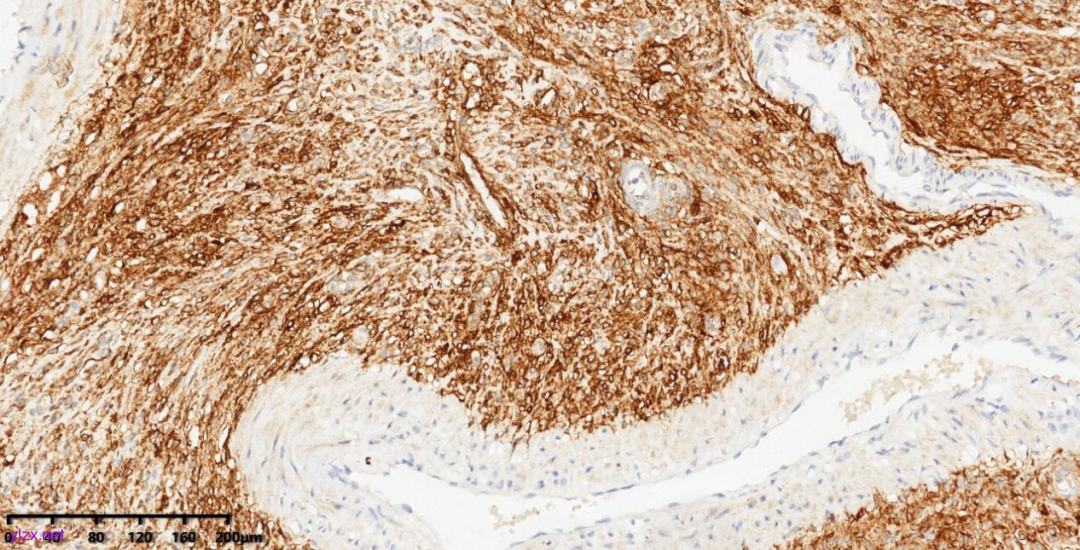

HMB45、Desmin、Caldesmon、SMA、ER、PR、CD10阳性表达,MeLanA、Cyclin D1阴性,ki-67增值指数低(约2%)。

图11 肿瘤细胞HMB45胞浆阳性

【免疫表型】:

PEComas表达黑色素细胞标记(如HMB45、melan-A和MITF)以及肌源性标记(如SMA、desmin和caldesmon),Desmin和h-caldesmon的阳性程度往往低于SMA。A组瘤细胞主要表达HMB45,而很少表达肌源性标志物;B组瘤细胞主要表达肌源性标志物,小部分表达 HMB45。黑色素细胞标志物表达在上皮样肿瘤细胞中比在梭形肿瘤细胞中更常见。子宫肉瘤样PEComa以表达色素细胞标记为主。大约15%的病例的肿瘤细胞TFE3核强阳性,TFE3重排的PEComas多发生在年轻患者中,具有显著的腺泡状生长模式和上皮样形态,并且经常不表达平滑肌标志物。